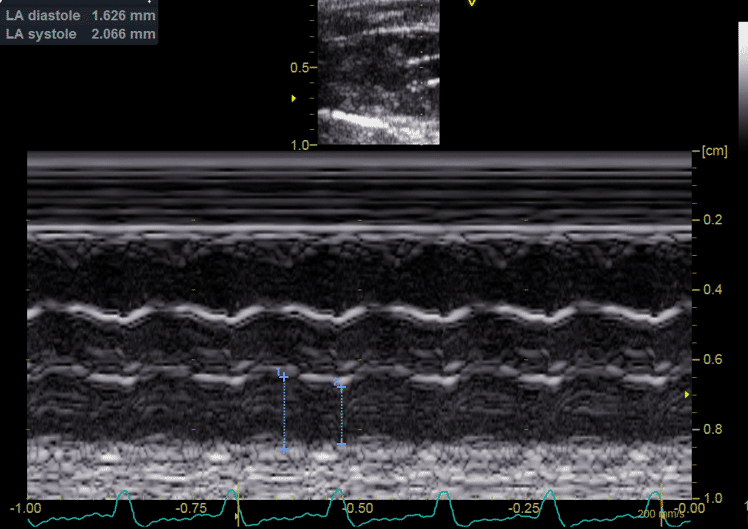

• fonction ventriculaire diastolique;

• évaluation des chambres cardiaques;